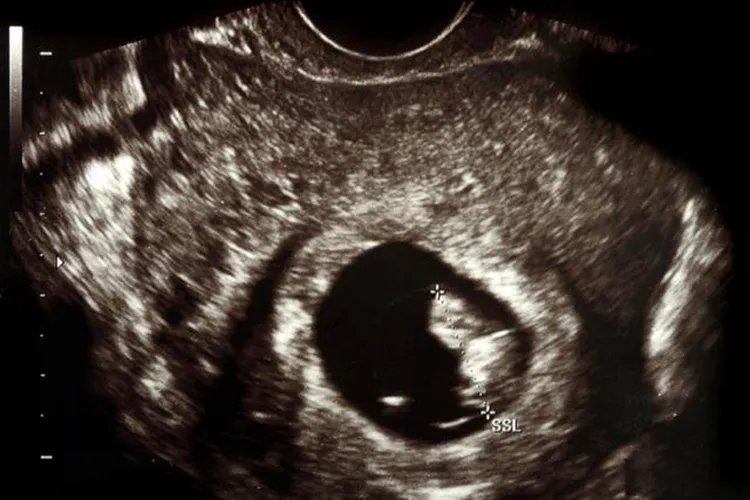

怀孕一个多月B超图片

的有关信息介绍如下:概述怀孕一个多月一般为怀孕4-8周,属于孕早期,B超检查可发现圆形或椭圆形妊娠囊。怀孕一个多月可通过B超检查明确宫内妊娠、判断胚胎着床状态,同时进行其他辅助检查。B超表现怀孕一个多月一般为怀孕4-8周,属于孕早期,B超检查的主要目的是确定宫内妊娠,排除异位妊娠、滋养细胞疾病、盆腔肿块等,阴道B超较腹部B超可提前近1周确定早期妊娠。怀孕一个多月行B超检查,可以确定胎数,若为多胎,可通过胚囊数目和形态判断绒毛膜性。B超检查还可用于估计孕龄,停经35日左右,B超检查时宫腔内可见到圆形或椭圆形妊娠囊,怀孕6周时,可见到胚芽和原始心管搏动,测定头臀长度可较准确地估计孕周。